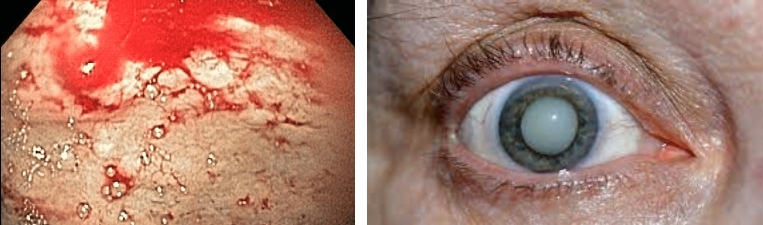

Já vi imagens chocantes: rins completamente destruídos em pessoas que foram diagnosticadas com diabetes há apenas dois anos. Antigamente, pensava-se que esse tipo de nefropatia ocorria apenas em pacientes gravemente doentes e de longa data. Hoje, infelizmente, nós a encontramos mesmo em pacientes com pré-diabetes. Por isso, eu digo: não espere que o corpo comece a gritar, quando já for tarde demais. Ouça-o antes. E ajude-o com o que o cura, não com o que o suprime.

Olhe para estas imagens. Elas são as consequências para aqueles que ignoraram os sintomas. Você realmente quer arriscar o mesmo fim?

— Cada uma dessas pessoas pensou: "Isso não vai acontecer comigo." Mas a realidade está diante dos nossos olhos: dano celular, oxidação de órgãos, sofrimento... e no final, uma morte silenciosa. Mais de 90% das pessoas que nos deixaram não agiram a tempo. A glicose destrói por dentro e o faz invisivelmente. Ignorar os sintomas significa, passo a passo, desistir da sua vida.